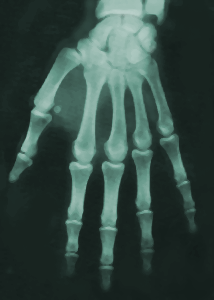

| A la naissance,

certaines zones du squelette se présentent encore sous forme

cartilagineuse (non visibles à la radiographie) et vont

progressivement s'ossifier pour devienir opaques aux rayons X. Ici

le poignet ne montre aucune structure osseuse visible alors même

que les os du carpe sont présents sous forme d'ébauches

cartilagineuses. |

Au moment du pic pubertaire de croissance, un

adolescence présente encore beaucoup de cartilages de croissances

au niveau des diaphyses des os longs. Ils sont la preuve d'une

croissance non treminée. Les os du poignet sont ossifiés mais leur

maturation n'est pas encore terminée. |

A l'âge adulte, les os ont terminé leur maturation.

Toutes les structures cartilagineuses sont ossifiées et

parfaitement visibles à la radiographie : c'est le stade finale de

maturation. |